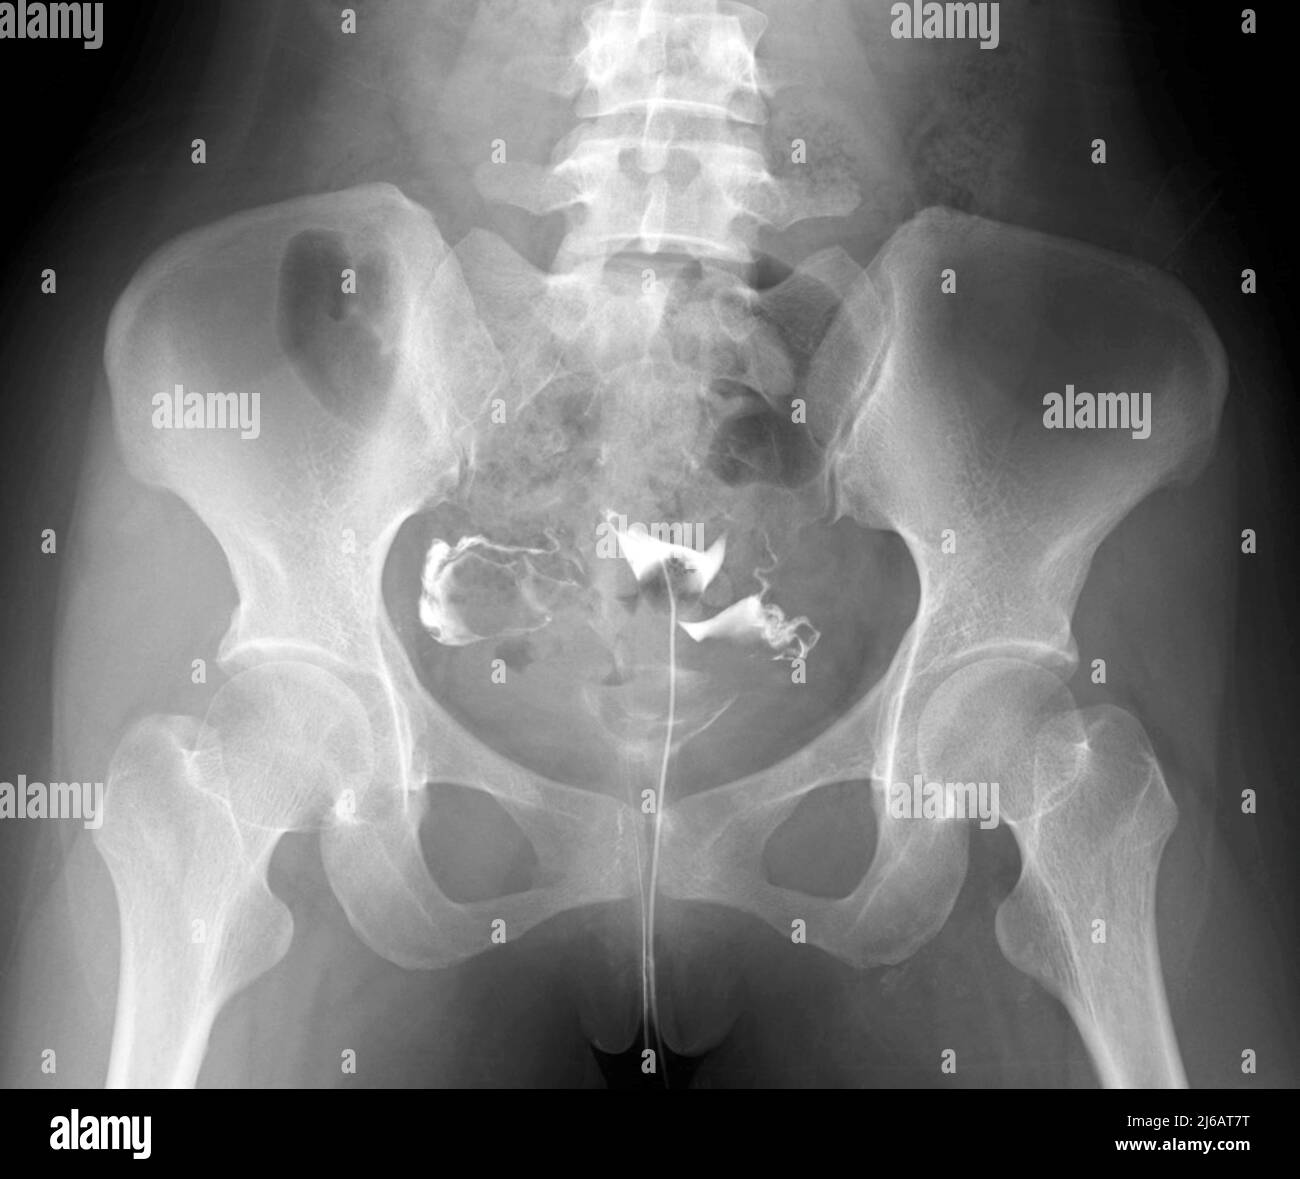

From www.sciencephoto.com

Blocked fallopian tube, Xray Stock Image M850/0651 Science Photo Dye X Ray Fallopian Tubes Hysterosalpingography (hsg), also known as uterosalpingography, [ 1 ] is a radiologic procedure to investigate the shape of the uterine cavity. Once the area is numbed, your ob/gyn will use a small, thin tube or catheter to insert liquid dye into your cervix, which is used to see the outline of your uterus and fallopian. It often is used to. Dye X Ray Fallopian Tubes.